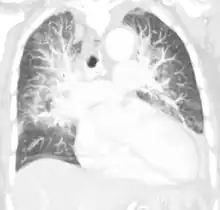

| Pulmonary edema with small pleural effusions on both sides | |

Low oxygen saturation in blood and disturbed arterial blood gas readings support the proposed diagnosis by suggesting a pulmonary shunt. A chest X-ray will show fluid in the alveolar walls, Kerley B lines, increased vascular shadowing in a classical batwing peri-hilum pattern, upper lobe diversion (biased blood flow to the superior parts instead of inferior parts of the lung), and possibly pleural effusions. In contrast, patchy alveolar infiltrates are more typically associated with noncardiogenic edema[3]